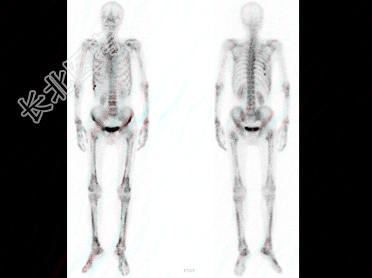

多项选择题男,67岁, 诉全身多处疼痛4月余,行全身骨显像如图。对此影像的描述下列正确的有 ( )

A、提示患者有慢性肺部疾患

B、提示原发病可能为肺癌

C、有双轨征

D、有严重的骨质疏松

E、正常的骨影像